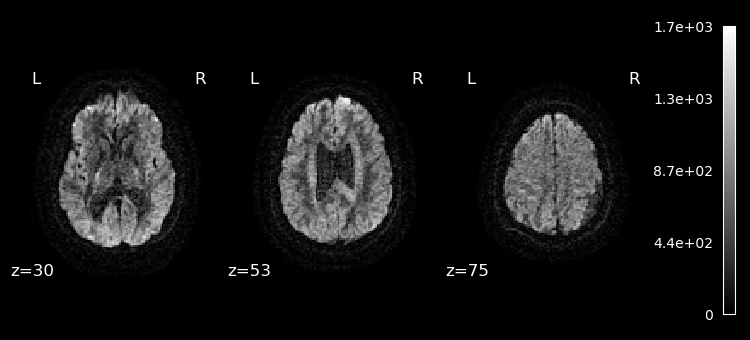

Lets plot the first 10 volumes.

%matplotlib inline

from nilearn import image

from nilearn.plotting import plot_epi

selected_volumes = image.index_img(dwi, slice(0, 10))

for img in image.iter_img(selected_volumes):

plot_epi(img, display_mode="z", cut_coords=(30, 53, 75), cmap="gray")